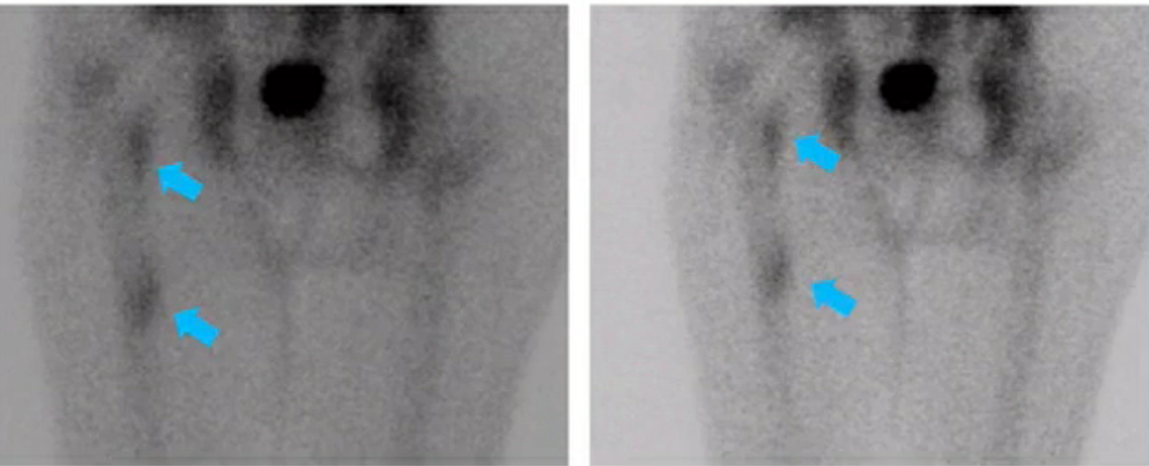

painful scoliosis

osteoid osteoma in the posterior elements